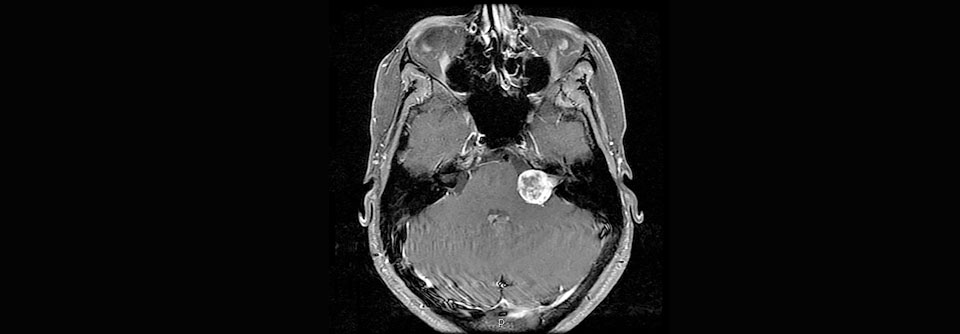

Primäre Hirntumoren neu klassifiziert: Wann ist ein Gliom ein Glioblastom?

In naher Zukunft soll eine neue WHO-Klassifikation für Hirntumoren erscheinen. Die wichtigsten Neuerungen umfassen unter anderem die molekulare…

Onkologie und Hämatologie , Neurologie